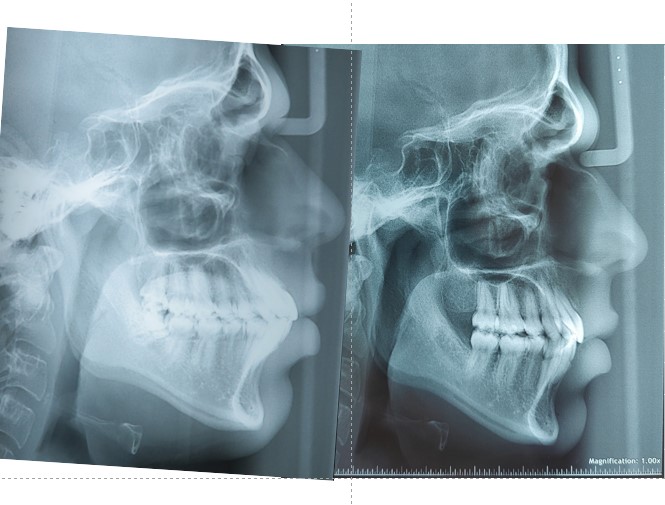

Pre & Post Rx Xray’s-

Dental Improvements

- Full resolution of crowding

- Proper space closure with good root control

- Improved overjet and overbite

- Stable Class I occlusion

Facial Aesthetics

- Noticeable reduction in upper and lower lip protrusion

- Soft-tissue profile became more balanced